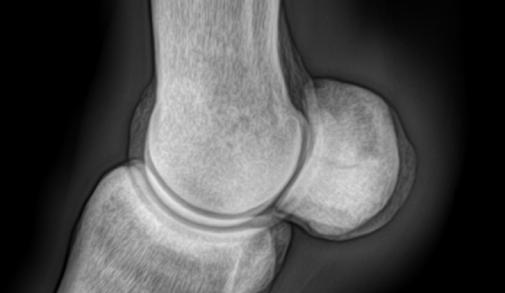

Joint structure

Articular cartilage Synovial membrane Bone Bone Articular capsule Joint cavity containing synovial fluid © ANATOMY & PHYSIOLOGY –OPENSTAX COLLEGE.